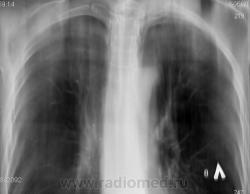

Справа на верхушке инфильтративная тень. Слева в задних отделах мелкие буллы.

На последнем срезе тень в 1 сегменте, мелкие полости в верхних долях с обеих сторон.